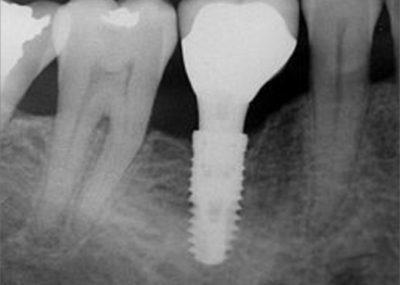

Comparable à une racine artificielle, l’implant dentaire est un petit objet cylindrique de la forme d’une vis qu’un chirurgien-dentiste fixe dans l’os maxillaire du patient. Deux a trois mois sont nécessaires à son intégration osseuse. Il remplace la racine de la dent perdue qui offre ainsi une base robuste pour accueillir une couronne, un bridge ou une prothèse dentaire amovible, et permettre au patient de mastiquer normalement et sans encombres.